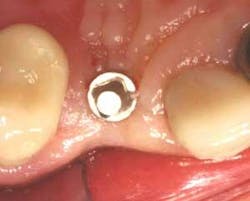

Figure 5 - Implant-abutment unit. The ISI implant-abutment unit is placed initially using fingers, followed by the Thumb Nob, then the wratchet. The depth was determined by both bone resistance as well as determination of margin height just below the soft-tissue margin.

Figure 6 - Implant-abutment unit occlusal view. Occlusal view of the ISI implant-abutment unit.